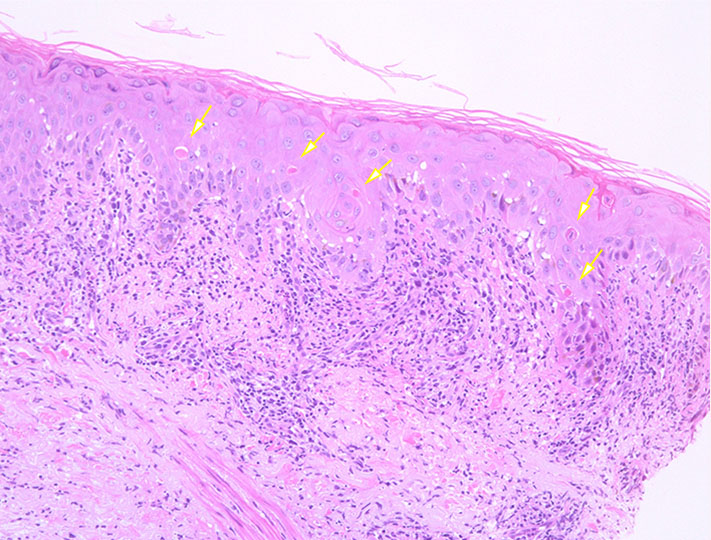

• Epidermotropism 表皮向性が最重要な所見 (表皮への親和性affinityを示すことで以前はMFにおいて限定して使用されていた(狭義の表皮向性)

• 狭義のEpidermotropism表皮向性にあてはまる5つの所見

• 多数の浸潤リンパ球が表皮内に不均衡に分布する disproportionate epidermotropism

• 表皮に入ったリンパ球が真皮リンパ球よりも大きい large epidermal lymphocytes (emperor sign)

• 表皮に入ったリンパ球がハロー(halo)を有する haloed lymphocytes

• haloをもつ異型リンパ球が基底層に並ぶ(string of pearls distribution ) basilar lymphocytes

• Pautrier's microabscess (Pautrier微小膿瘍)

• string of pearlsの進展は(1)-->(3)の順にすすむと推察される.*3

(1)基底層に2-3個のみhaloをもつ異型リンパ球が出現

(2)haloのより明瞭な異型リンパ球が横への広がりを見せる

(3)異型リンパ球が数珠状に連続するとともにhalo内に4個以上異型リンパ球が含まれるPautrier's microabscessの形成も見つかる